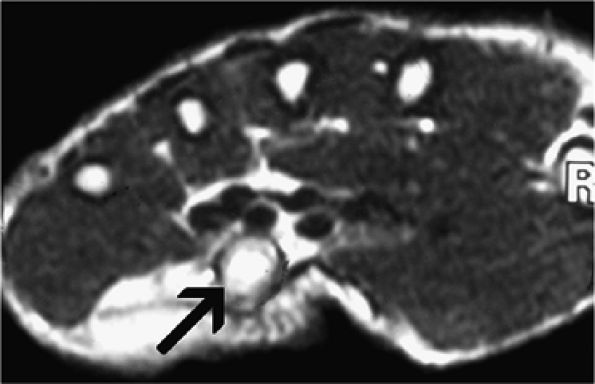

FIGURE 12.49 ● Ganglion cyst compressing the ulnar nerve. Axial (A) and oblique coronal (B) fat-suppressed T2-weighted images demonstrate a ganglion cyst (arrows) within Guyon's canal.